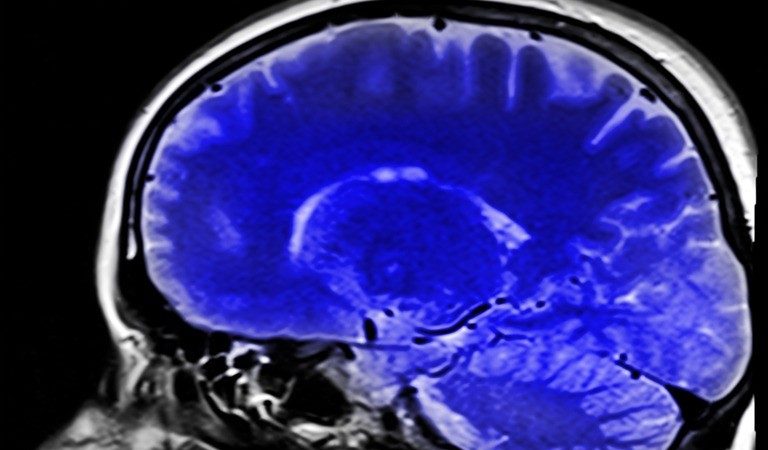

Врач отметила, что медленное размеренное дыхание очень хорошо влияет на состояние мозга.

С помощью дыхательных упражнений можно снизить уровень бета-амилоидных пептидов и приостановить формирование амилоидных бляшек, провоцирующих развитие болезни Альцгеймера, подчеркивает эндокринолог.